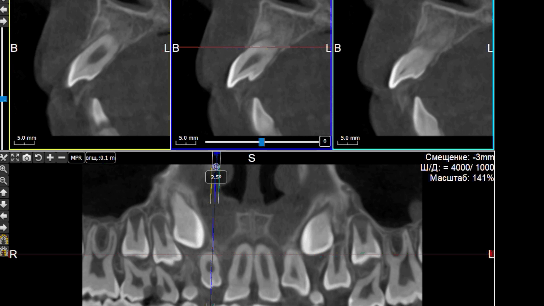

На КЛКТ на руках у матери пациента от сентября 2024 года зубы 1.1, 2.1 в стадии незакрытой верхушки корня, определяются признаки конвергенции корней в апикальной части и дивергенции коронок, признаки горизонтальной деструкции костной ткани до 23 длины корня, признаки расширения пространства периодонтальной связки, признаки наличия симптома «костной ступеньки», свидетельствующего о предполагаемом местоположении ретгеннеконтрастных эластических колец в тканях пародонта. Инструментом «линейка» определено расстояние от режущего края зуба до предполагаемого местоположения эластических колец (Рисунки 4, 5).

Рисунок 4. Кросс-срезы КЛКТ зубов 1.1, 2.1 (анимация).